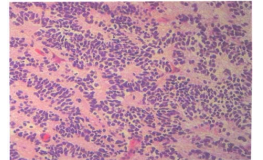

98 一名 8 歲男孩,突然發生頭痛、嘔吐及步態不穩,電腦斷層掃描發現水腦症及後顱窩的中線腫瘤, 手術時該腫瘤侵犯第四腦室及其頂端,顯微鏡檢查所見如附圖,其診斷應是: (A)聽神經瘤(Acoustic neuroma) (B)腦膜瘤(Meningioma) (C)血管母細胞瘤(Hemangioblastoma) (D)髓母細胞瘤(Medulloblastoma)